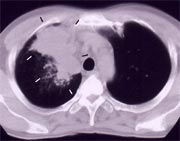

胸部CT検査

エックス線を使用し、コンピュータで計算して体内の詳細な画像を作成する方法です。CTとはコンピュータ断層撮影(コンピューテド・トモグラフィー)の略です。胸や肺を輪切りにして詳細に検討できます。

左写真が胸部CT写真です。黒いところが肺で、いびつで類円形な白い部分が肺がんです。